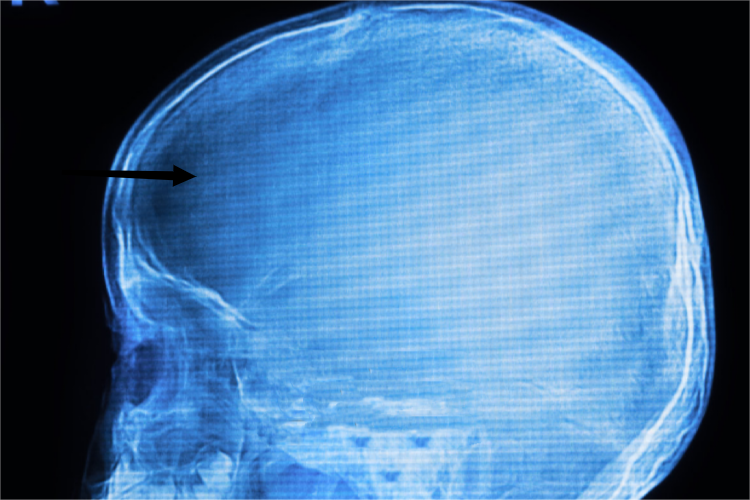

三岁孩子头骨正常情况下头围约48.5厘米,可随年龄逐渐增加,直至18岁左右基本无变化。正常头骨的矢状缝和其他颅缝都正常骨化闭合,头部外形正常,无异常活动,无压痛和异常的隆起、凹陷、畸形等表现。

头骨大小异常、畸形,或有异常活动,可成为一些疾病的典型体征,应及时就医检查治疗。如三岁孩子头骨周长明显不足48.5厘米,相较同龄人小,可能是小颅。如前额左右突出,头顶平坦呈方形,可见于小儿佝偻病或先天性梅毒。如额、顶及枕部突出膨大呈圆形,对比之下颜面很小,还有双目下视、巩膜外露的特殊表情,可见于脑积水。